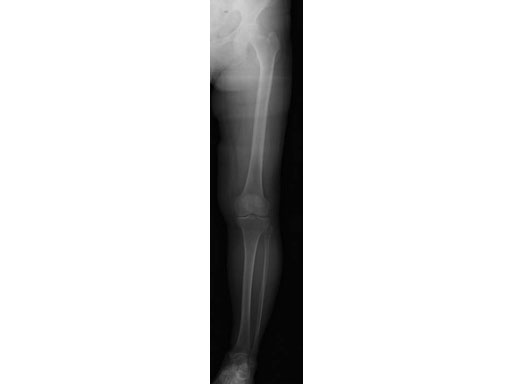

65-year-old female. Osteoarthritic patient complaining of medial knee pain of her left knee.

Case provided by Takeshi Sawaguchi, Toyama, JP

Follow-up in this case is short, because the TomoFix small only became available in August 2008.